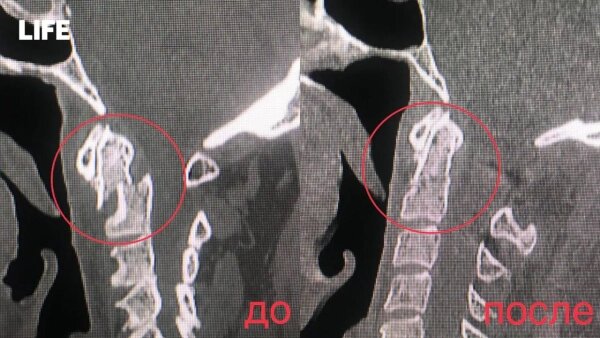

В Видновскую клиническую больницу скорая доставила 64-летнего мужчину с серьёзным повреждением шеи, рассказали Life.ru в медучреждении. Дома он неудачно поскользнулся, после чего его состояние резко ухудшилось: кружилась голова, сознание путалось, реакции затормаживались, руки и ноги слабели и немели. Обследование показало нестабильный перелом второго позвонка с осколками, смещением и сжатием спинного мозга.

Как пояснил нейрохирург Сергей Шипилин, такую травму называют «переломом висельника» — зловещее прозвище, намекающее на её тяжесть. Обычно она обрекает человека на инвалидность, а то и на смерть, но срочная операция переломила судьбу пациента. Ему вернули способность двигаться, оставив лишь лёгкие ограничения в поворотах шеи.

Хирургам пришлось филигранно вправить смещённые позвонки, зафиксировав их винтами с двух сторон, а заодно провести ламинэктомию первого позвонка — убрать его часть, чтобы освободить спинной мозг от давления. Операция на шейном отделе, по словам врачей, — это ювелирная работа, где нет права на ошибку.